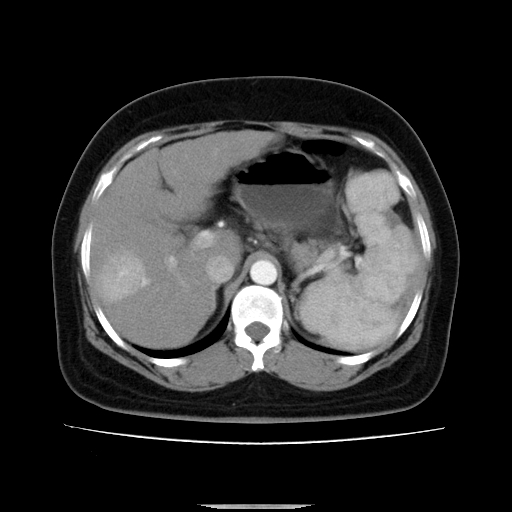

标题: CT14225:女性46岁。当地B超示肝内占位,来我院作CT检查。请 [打印本页]

标题: CT14225:女性46岁。当地B超示肝内占位,来我院作CT检查。请

肝内结节强化特点符合原发性肝癌表现,脾脏改变考虑为增大及先天发育所致。

动脉期病原灶明显强化高于肝密度且中央有无强化区,静脉期强化程度下降明显,延迟低于肝密度,考虑肝腺瘤可能性大,

符合肝癌表现,脾脏大(肝硬化?)

肝内结节强化特点:快进快出符合原发性肝癌表现

此患者虽然符合快进的特点,却不符合快出的特点,因为门脉期几乎是等密度,不符合肝癌的增强表现,所以我考虑肝局灶性结节增生可能性大

肝内结节强化特点符合原发性肝癌表现。脾大。

快进快出,符合肝癌表现。脾脏改变考虑为增大及先天发育所致。